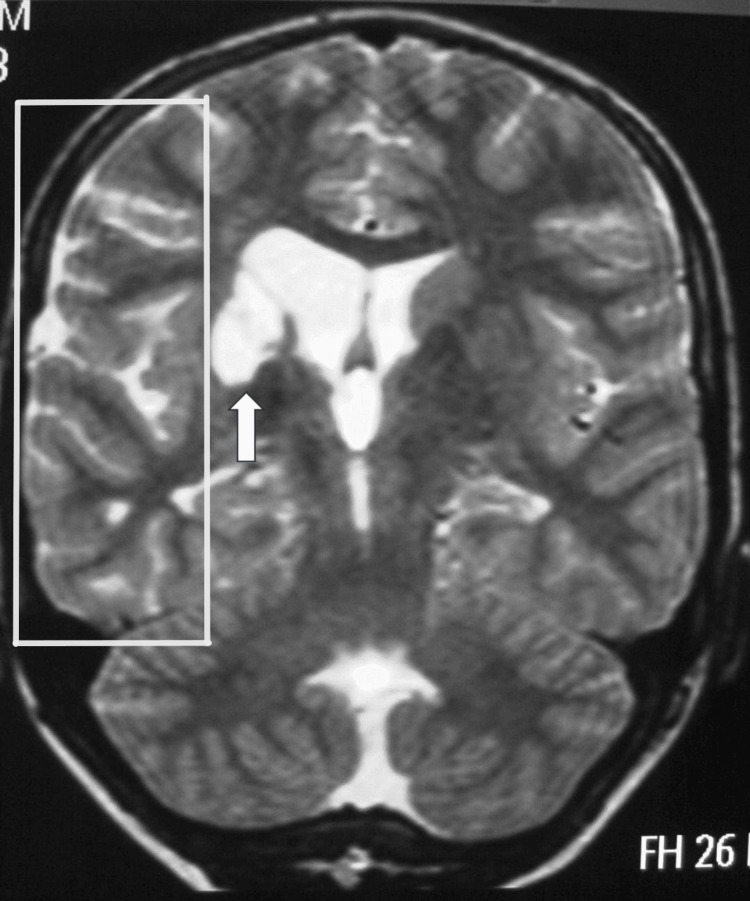

烟雾病(MMD)是一种罕见的脑血管疾病,其特征是双侧颈内动脉和大脑前动脉收缩或阻塞,导致缺血或出血事件。一位28岁的白人女性,有双侧烟雾病史,在怀孕38周时接受剖宫产。手术前后的处理包括停用阿司匹林,密切监测血流动力学,并给予全身麻醉。一个健康的男婴通过剖宫产分娩,母亲和婴儿在第三天出院,没有任何并发症。该病例是希腊首次记录的妊娠期烟雾病病例。通过早期识别、量身定制的分娩计划以及产科、神经病学和麻醉团队之间的协作护理,有可能取得成功的结果。需要更多的多中心研究来为这一高危患者群体制定标准的管理方案。

Moyamoya disease (MMD) is a rare cerebrovascular disorder characterized by the constriction or obstruction of the internal carotid and anterior cerebral arteries bilaterally, leading to either ischemic or hemorrhagic events. A 28-year-old Caucasian female with a history of bilateral MMD was admitted for a scheduled cesarean delivery at 38 weeks of pregnancy. The management around the surgery involved stopping aspirin, closely monitoring hemodynamics, and administering general anesthesia. A healthy male baby was delivered via cesarean section, and both the mother and infant were discharged on the third day without any complications. This case represents the first recorded instance of MMD during pregnancy in Greece. Achieving successful results is possible through early identification, tailored delivery planning, and collaborative care among obstetrics, neurology, and anesthesia teams. Additional multicenter research is necessary to create standard management protocols for this high-risk patient group.